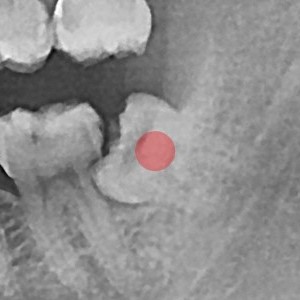

智齿拔除 部分埋伏智齿